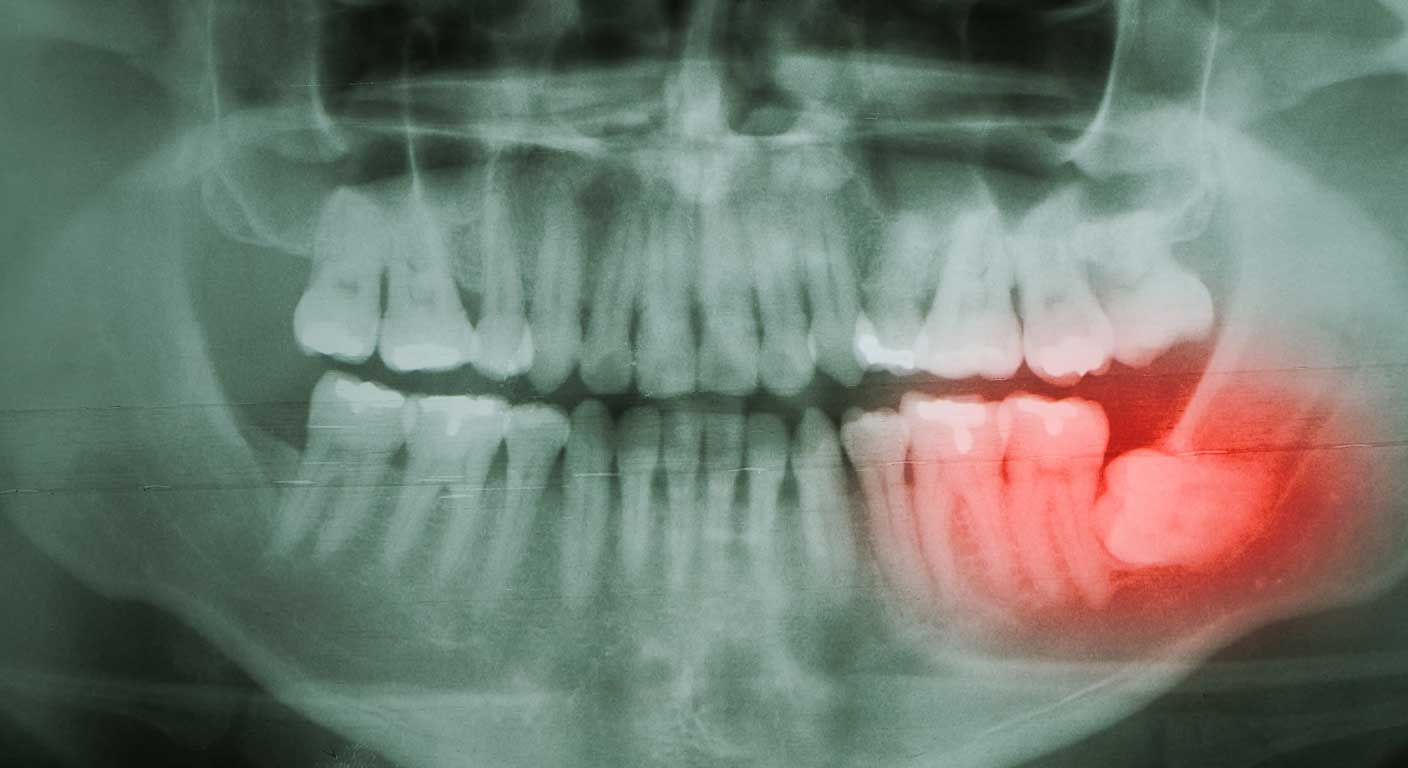

دندان عقل نهفته

دندان عقل نهفته یکی از شایع ترین مشکلات دهان و دندان است که بسیاری از افراد در اواخر